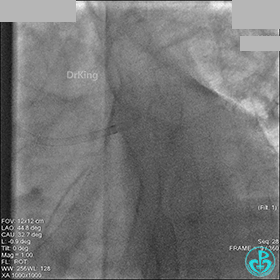

1周后再次上台,右冠脉3级血流,3段局限性严重狭窄,内膜模糊,应该是上次操作夹层遗留下的血肿。

先处理前降支开口严重狭窄并顺利植入前降支到左主干支架。